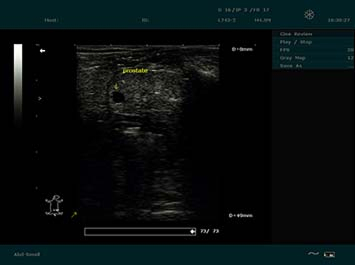

Imágenes Clínicas